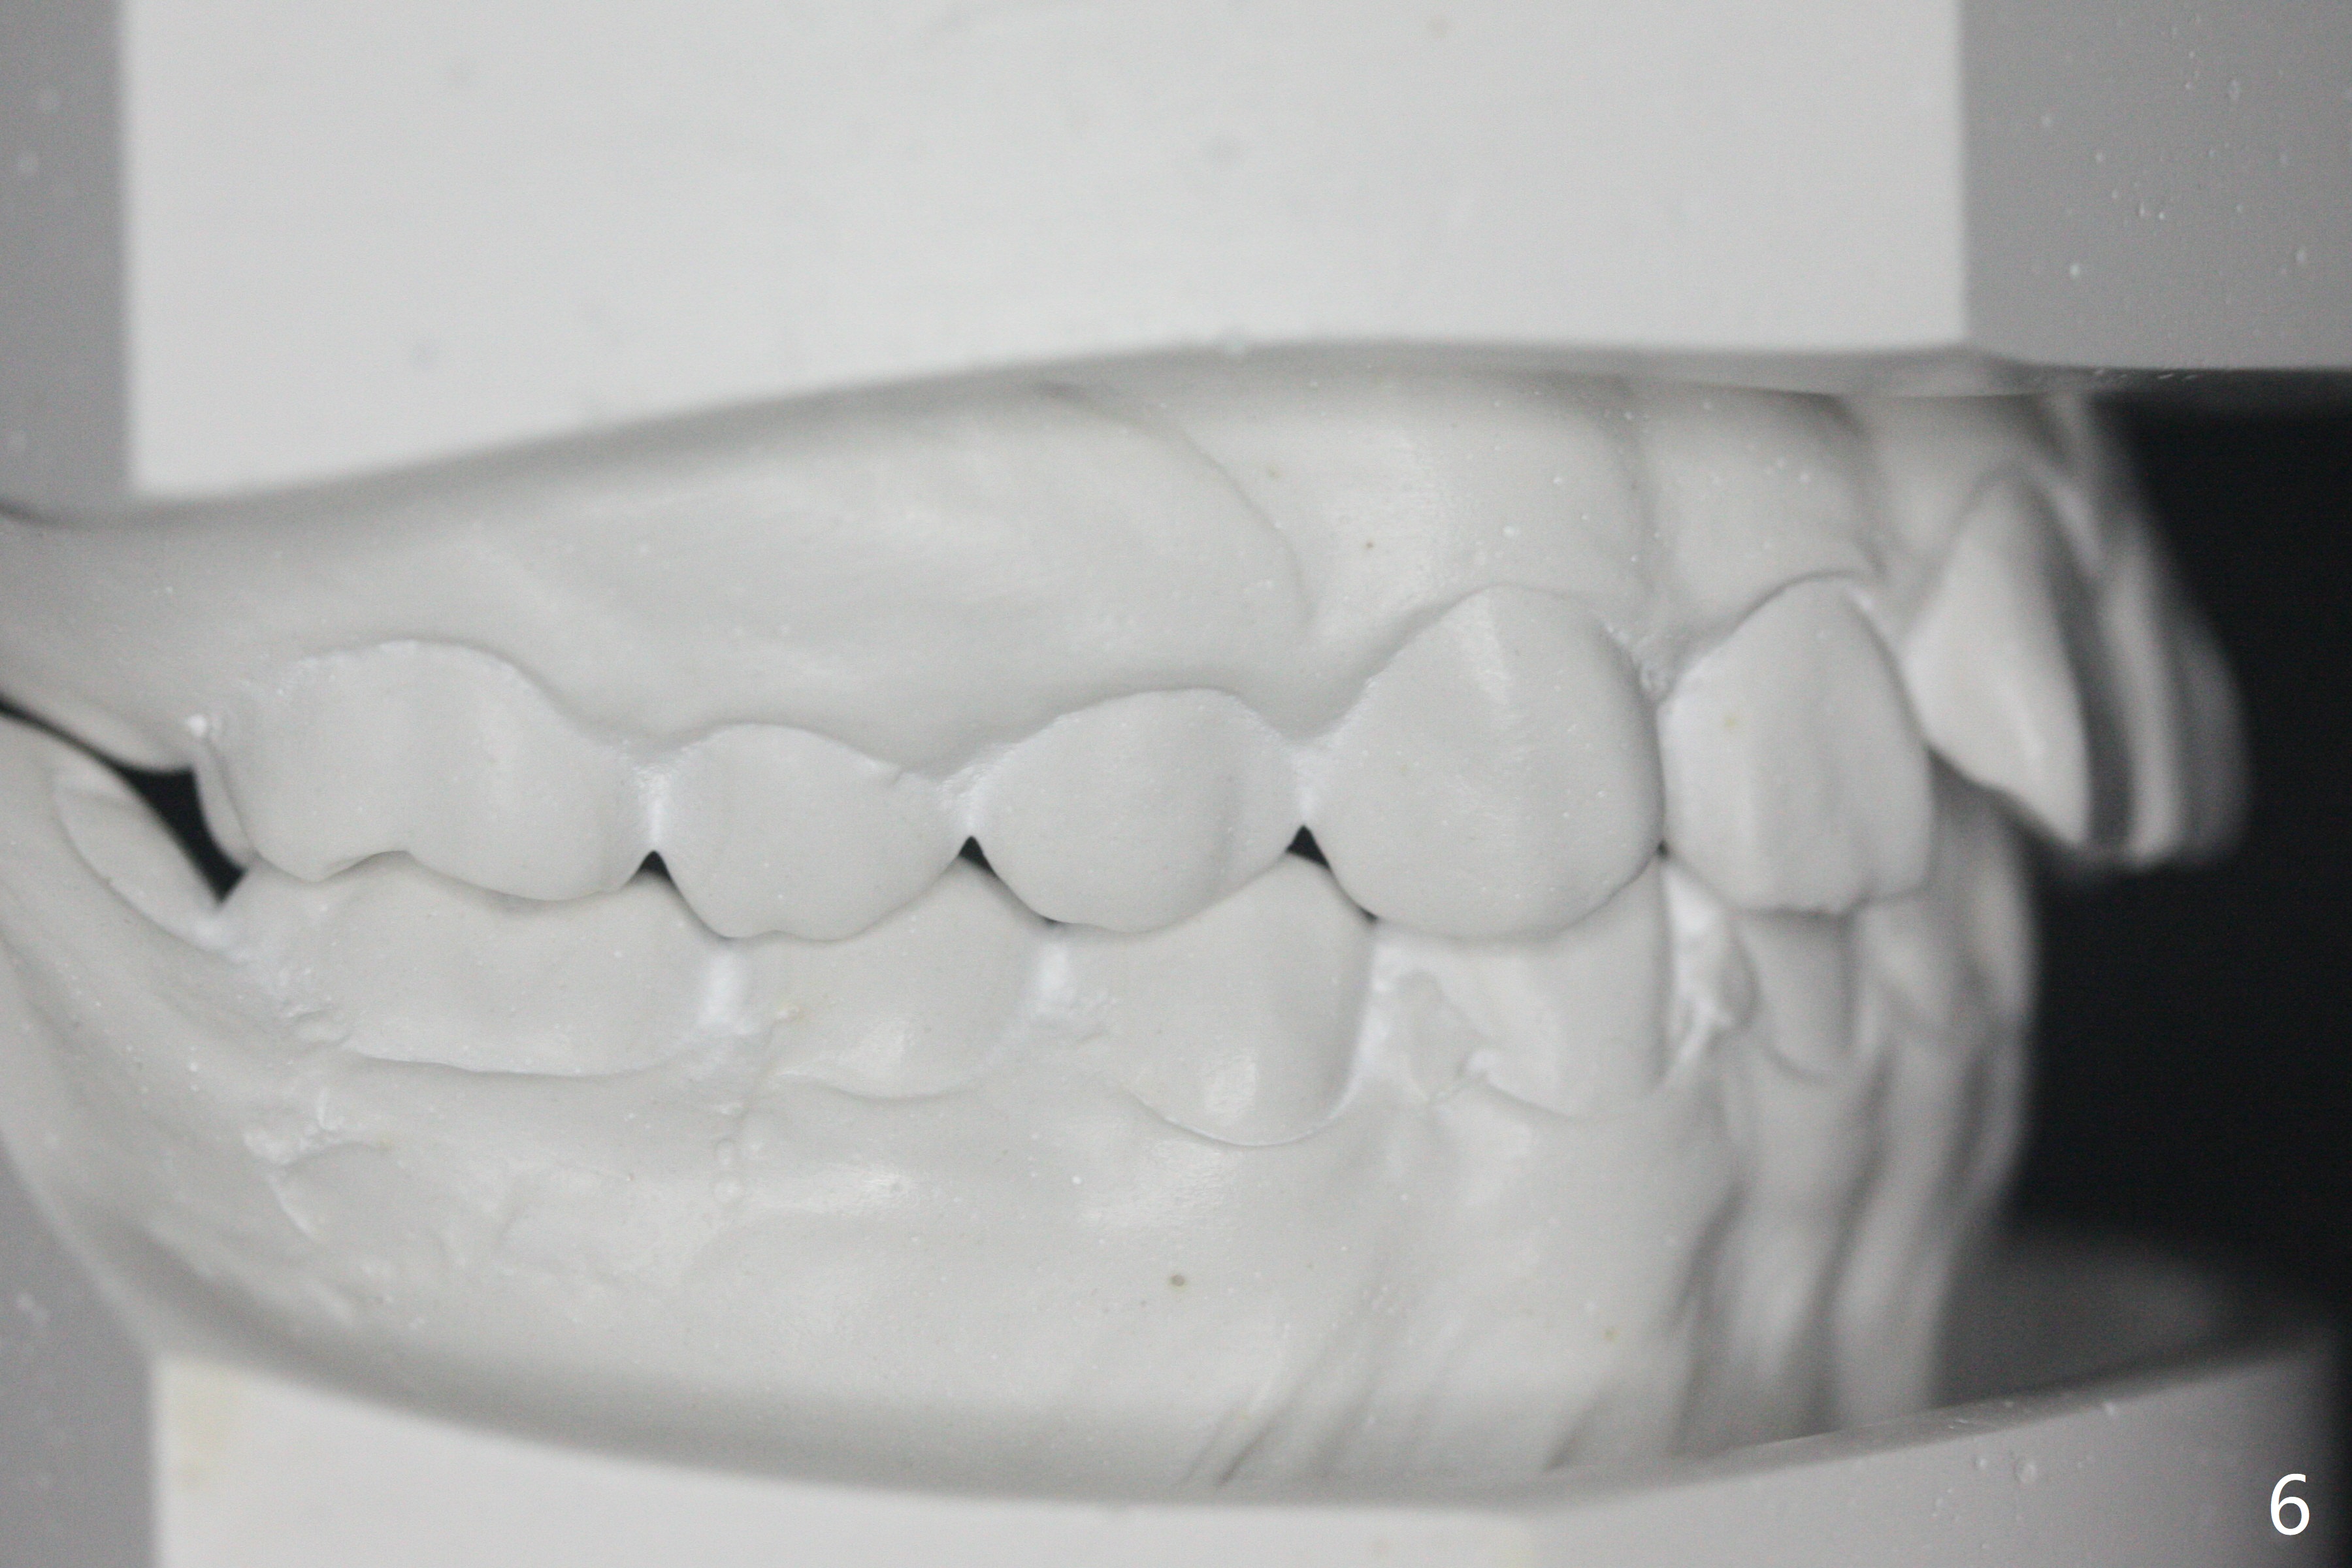

Facial Class I Occlusal Class II

A 12-year-old woman has Class I facial profile (Fig.1-4,12,13) and apparently Class II Division I malocclusion (Fig.6-11). Start Class II retraction as early as possible to take advantage of the upper and lower posterior diastemata (Fig.9,11 (in fact there is no diastema)). LL7 impaction is noted immediately prebanding (Fig.14). Surgical access is pending.